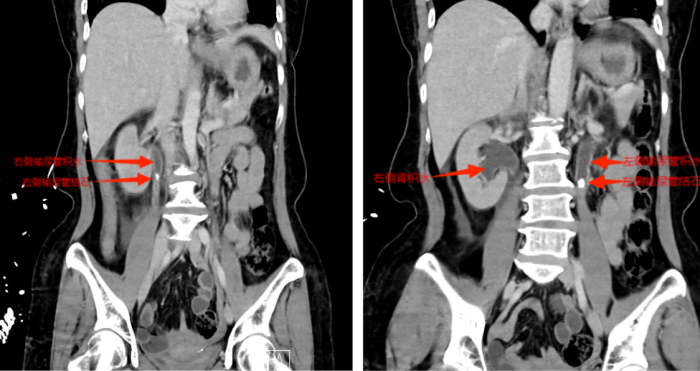

等到第二天送医时,张小华血压已降至78/42mmHg(血压<90/60mmHg称为休克血压),CT结果显示其双侧输尿管结石引发尿路梗阻,导致尿源性脓毒血症合并脓毒性休克。医院立即启动MDT多学科诊疗,泌尿外科一区主任傅发军带领团队紧急在急诊ICU实施床旁输尿管支架置入术,迅速解除梗阻,经抗感染等综合治疗,患者最终转危为安。目前,张小华已康复出院,择期再返院处理双侧输尿管结石。

CT显示双侧输尿管结石、肾积水

双侧输尿管支架置入后解除尿路梗阻